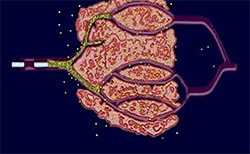

Při vyšetření jaterní tkáně pod mikroskopem je patrná struktura tvořená sítí jednotek, které se nazývají jaterní lalůčky. Jaterní lalůček je malý a má vzhled šestihranného cylindru. Je obklopen pojivovou tkání a na okrajích je spojen s cévními strukturami. Tyto cévy zahrnují větve portální žíly, jaterní tepny a žlučové kanálky. Středem lalůčku prochází centrální žíla, která je obklopena pruhy jaterních buněk, jež se paprskovitě rozbíhají na všechny strany. Mezi těmito pruhy se nachází široké tenkostěnné cévy. Veškerá krev z jater se sbírá do jaterní žíly, která se napojuje do krevního oběhu organizmu.

Krev přitéká do jater jaterní tepnou (obsahuje okysličenou krev ze srdce) a portální žilou (krev s živinami vstřebanými ze střeva), dále proudí do jaterních sinusoid a do centrální žíly, odtud pak ven z jater.

Obrázek 2: Struktura jaterního lalůčku (zvětšeno 1 000x)